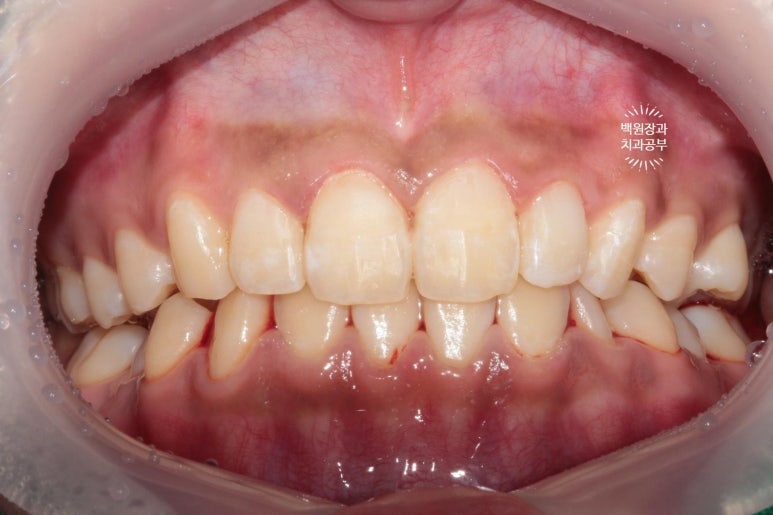

딱 봐도 잇몸이 부어 있으신 상태였습니다. 흡연자로써 치은연하치석 (잇몸 아래에 위치한 치석)이 많아 치주질환이 심하였고, 더불어 치태 관리가 되지 않아 충치도 여러군데 있었어요... 젊은 분이셨는데..

무려 저렇게 부었던 잇몸도 깔끔하게 돌아옵니다...!...

지금 잇몸 상태가 치석제거와 잇몸치료를 모두 완료한 직후입니다.

흡연으로 인한 약간의 잇몸 착색은 있지만, 붉고 부어 있었던 잇몸은 온데간데 없고, 너무나 깨끗한 잇몸상태를 되찾았죠...? 잇몸의 색깔은 선홍색으로 돌아왔고, 날씬하고 얇아진 모습입니다.

이것이 바로 잇몸치료의 위엄입니다!.. 치주과 전문의가 대표원장인 저희 치과에서 가장 많이 행하는 치료이기도 합니다.